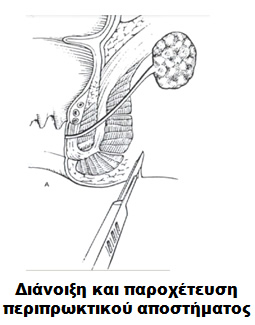

Χειρουργική επέμβαση για τη νόσο Crohn μπορεί να γίνει είτε σε επείγουσα βάση, άμεσα είτε προγραμματισμένα. Η πρώτη περίπτωση αφορά σε ασθενείς των οποίων η κατάσταση επιδεινώνεται αιφνιδιαστικά ούτως ώστε μέσα σε λίγες ώρες από την επίσκεψή τους στο νοσοκομείο να διαθέτουν την απόλυτη ένδειξη για να υποβληθούν άμεσα σε χειρουργείο. Συνήθως, οι ασθενείς αυτοί παρουσιάζονται είτε με διάτρηση του εντέρου (δηλαδή μία τρύπα στο έντερο με αποτέλεσμα ποσότητα κοπράνων ή άλλου εντερικού περιεχομένου να «χύνεται» μέσα στην κοιλιακή χώρα) είτε με πλήρη απόφραξη του εντέρου. Και οι δύο αυτές καταστάσεις είναι δυνητικά απειλητικές για τη ζωή του ασθενούς. Άμεση χειρουργική επέμβαση ενδέχεται να χρειαστεί και ένας ασθενής που λόγω της νόσου έχει αναπτύξει ένα περιπρωκτικό απόστημα και ο κίνδυνος πρόκλησης περαιτέρω βλάβης στους γύρω ιστούς ή εξάπλωσης της λοίμωξης καθιστά αναγκαία την παροχέτευσή του.

Μία χειρουργική επέμβαση στον πρωκτό για τη νόσο του Crohn ως επί το πλείστον λαμβάνει χώρα για την παροχέτευση ενός αποστήματος. Κατά τη διάρκεια του χειρουργείου, ο εξειδικευμένος χειρουργός παχέος εντέρου και πρωκτού «ανοίγει» τη μολυσμένη κοιλότητα και το υγρό περιεχόμενό της (πύον) εξέρχεται. Σε περιπτώσεις όπου η λοίμωξη παραμένει, το υγρό (πύον) εξακολουθεί να παράγεται προκαλώντας τη δημιουργία συριγγίου στην πάσχουσα περιοχή του πρωκτού.